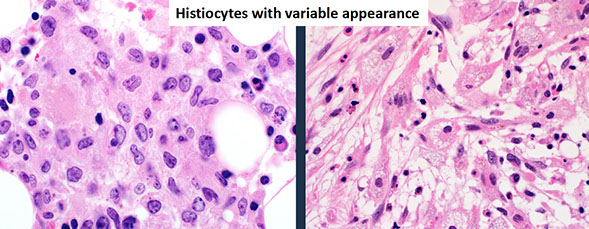

Histiocytic sarcoma

Micro: increased plasma cells

- plasma cells may be morphologically unremarkable ("Marshalko type")

- may be multinucleated (binucleate plasma cells can be seen in reactive conditions, although the more of these you see the more you think that it is neoplastic)

- may have visible nucleoli

- variant morphologies exist (lymphoplasmacytic, cleaved, anaplastic, blastic, etc.)

40-50% of cases lack IGH translocations